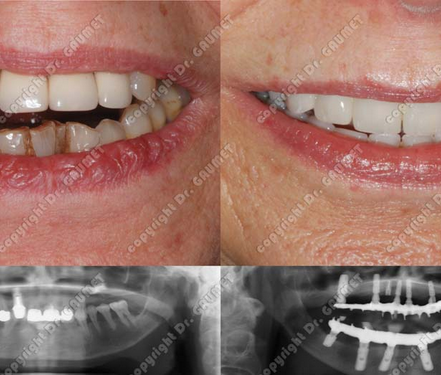

Situé au cœur du Flon à Lausanne, le cabinet du Dr Pierre Gaumet, spécialiste en parodontie et implantologie, est une adresse de confiance pour préserver et restaurer la santé de votre sourire. Fort de plus de 30 ans d’expérience et plus de 3 000 implants posés, le Dr Gaumet allie savoir-faire, sens esthétique et technologie de pointe pour offrir des traitements fiables, durables et confortables. Nous vous accueillons dans une atmosphère chaleureuse et rassurante, où l’écoute et le respect du patient sont au centre de chaque démarche.

Nous proposons une prise en charge complète, allant du traitement de la parodontite et des récessions gingivales, aux implants dentaires, en passant par les greffes osseuses, l’extraction des dents de sagesse et la réhabilitation esthétique du sourire. Grâce à la sédation consciente, même les patients les plus anxieux peuvent recevoir leurs soins en toute sérénité. Cette approche globale permet d’éviter des déplacements entre plusieurs spécialistes et garantit des solutions personnalisées, transparentes et adaptées à chaque situation, avec toujours la solution la moins invasive privilégiée.

- Esthétique du sourire

Relooking du sourire, réhabilitation complète, alignement, harmonisation et soins esthétiques pour un sourire naturel.